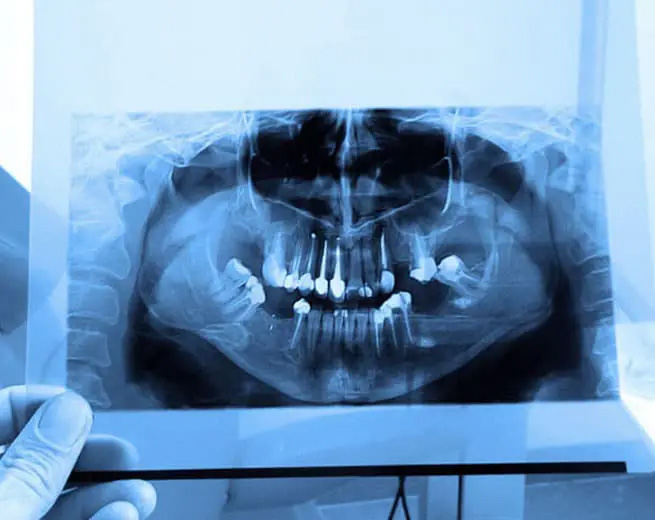

At Wayne T. Yee, DDS, panoramic imaging is a specialized dental X-ray technique that captures a two-dimensional, wide-angle image of the entire oral and maxillofacial region. Unlike intraoral X-rays focusing on individual teeth, a panoramic X-ray captures a broader view, showing both the upper and lower jaws, all the teeth, surrounding structures, and the temporomandibular joint (TMJ).

One of the primary benefits of panoramic imaging is its ability to provide a comprehensive view of the entire oral and maxillofacial region in a single image. This includes the teeth, jaws, temporomandibular joints (TMJ), sinuses, and other facial structures. Dentists can assess multiple areas simultaneously, leading to more accurate diagnoses and treatment planning.

Panoramic imaging is a diagnostic radiographic technique that produces a single, wide-view two-dimensional image of the entire oral and maxillofacial region. The image captures the upper and lower jaws, all of the teeth, the temporomandibular joints, and portions of the sinuses in one exposure. This noninvasive method gives clinicians a broad overview that supplements clinical examination and more focused intraoral X-rays.